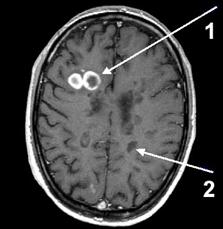

Діагноз визначається на підставі врахування анамнестичних, клінічних та лабораторних даних. Враховують вік пацієнта, прогредієнтність перебігу хвороби, багатовогнищевість ураження центральної нервової системи, що визначена при топічній діагностиці. Звертають увагу на нестійкість симптомів протягом доби, наявність феномену “клінічної дисоціації” — невідповідності порушення функції та об’єктивної неврологічної симптоматики. Важливими для підтвердження діагнозу є методи нейровізуалізації - комп’ютерна томографія та магнітно-резонансна томографія (МРТ) головного та спинного мозку (рис.2), дослідження викликаних потенціалів головного та спинного мозку різної модальності, імунологічні, імуногенетичні та біохімічні обстеження.